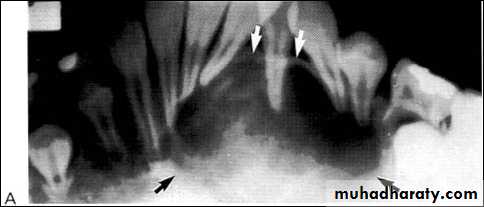

Central giant cell granuloma*A relatively uncommon, non- neoplastic mass in the jaws (intraosseous) producing an expansile radiolucent soap bubble appearance.

*Age; <20 years. Female > Male.

*Teeth are vital, with some root resorption & migration of teeth.

Multilocular appearance, expansion (arrowed) and considerable displacement of the adjacent teeth.

Buccal and lingual expansion (arrowed) and the undulating cortical border.